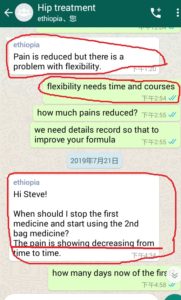

Following are some oversea patients recent feedback

Newly progresses(more will be uploaded soon)!

3. The gentleman in India just started May, 2019. Actually he started on April 28, 2019 but he used it in wrong way and got less effects, ONLY on May 8, 2019 during our follow-up, we found his wrong-doing, and then corrected him. ONLY in 2 days, his pains significantly reduced!!!!